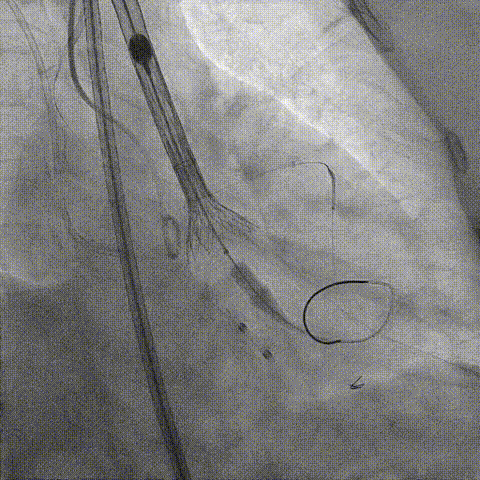

释放冠脉支架

释放瓣膜

造影评估

支架内后扩张

冠脉造影

根部造影

最终结果

检查结果-即刻超声

动脉瓣瓣周轻度反流。

经主动脉口收缩期血流最大速度约1.5m/s,最大跨瓣压差约10mmHg。